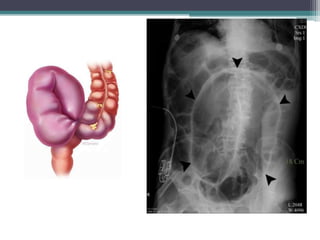

Tài liệu bàn về tắc ruột, bao gồm định nghĩa, phân loại và nguyên nhân của tình trạng này, với sự phân biệt giữa tắc cơ học và cơ năng. Các triệu chứng và chẩn đoán lâm sàng được trình bày, kèm theo phương pháp chẩn đoán cận lâm sàng như x-quang và siêu âm. Ngoài ra, tài liệu cũng đề cập đến các biến chứng và hậu quả của tắc ruột.